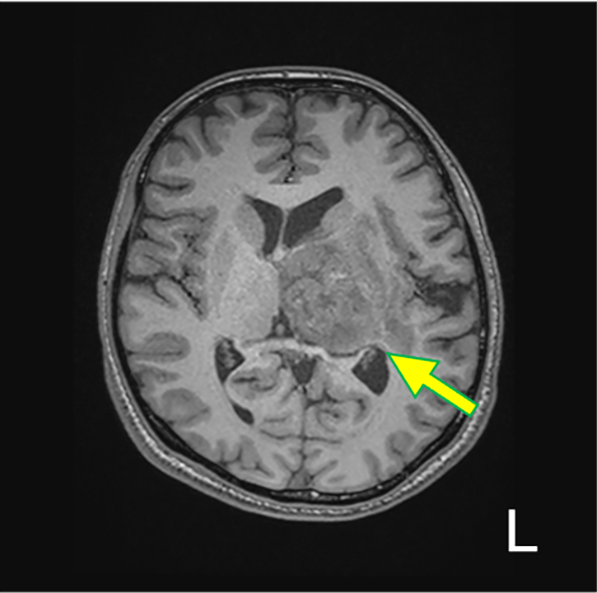

図1.T1WI(Tra.)

左視床を中心に、やや不均一な灰白質と同程度の信号を呈する腫瘤を認める(矢印)。mass effect を呈し、軽度の大脳鎌下ヘルニアを生じている。